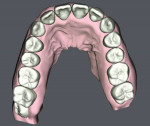

30-year-old female patient presented complaining of being embarrassed and insecure about her smile. Upon examination, the patient exhibited poor oral hygiene, bleeding, deep pockets, bone loss, and heavy subgingival and supragingival calculus. There was moderate-severe crowding in her maxillary arch with severe anterior cross-bite on teeth Nos. 7 and 10. A comprehensive treatment plan was presented and included stabilizing her periodontal condition and proceeding with SureSmile® Clear Aligners (Dentsply Sirona, suresmile.com) therapy. Clear aligner therapy was indicated over traditional brackets and wires due to hygiene concerns and the patient's existing periodontal condition. The case was completed with 35 aligners, attachments, and the adjunctive use of Chewies aligner tray seaters and SureSmile® VPro™, which were included in the SureSmile Complete package. The SureSmile aligner straight trimline design over the gingiva allowed for excellent traction and retention and minimal attachments. The patient experienced no gingival discomfort and tolerated the treatment well. Her smile was aligned to completion in 11 months with good traction and without refinement. The patient's periodontal condition and oral hygiene were improved with the overall effect of treating malocclusion. Today, the patient is proactive about her oral health, exhibits a confident, healthy smile, and is currently in retention therapy with SureSmile retainers.

SureSmile Clear Aligners therapy was able to predictably treat a moderate to severe anterior cross-bite case with minimal aligners and attachments, in a relatively short time period without refinement.